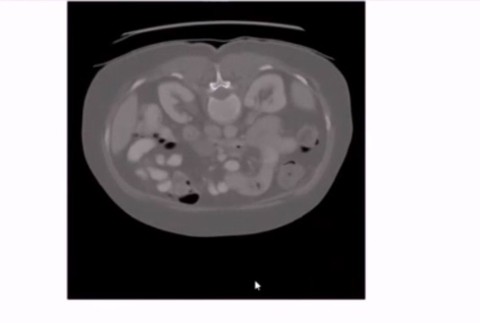

Mladý vedec menom Rishab, ohromil medikov po celom svete. Má len 13 rokov, pochádza z Oregonu a vymyslel spôsob, ako včas diagnostikovať rakovinu pankreasu a zachrániť tak život množstvu pacientov. Jedinečnosť jeho vynálezu spočíva v rýchlej lokalizácii orgánu. "Skúšal som svoje zariadenie na CT a magnetickej rezonancii. Algoritmus funguje cez umelú inteligenciu, ktorá dokáže veľmi rýchlo nájsť pankreas. Človek potom strávi pod žiareniím oveľa menej času než doteraz," uviedol mladý vedec Rishab Jain.

Aj podľa skúsených odborníkov nie je vždy jednoduché tento orgán v ľudskom tele nájsť. Systém z hlavy mladého vedca môže pomôcť nielen pri jeho kontrole, ale aj prípadnej operácii. "Aj skúseným rádiológom môže niekedy trvať niekoľko hodín, kým zistia, kde presne sa pankreas nachádza. Je veľmi zložité nájsť ho, pretože je za žalúdkom a hneď vedľa chrbtice, čo býva pri operáciách veľmi zložité," objasnil Rishab.